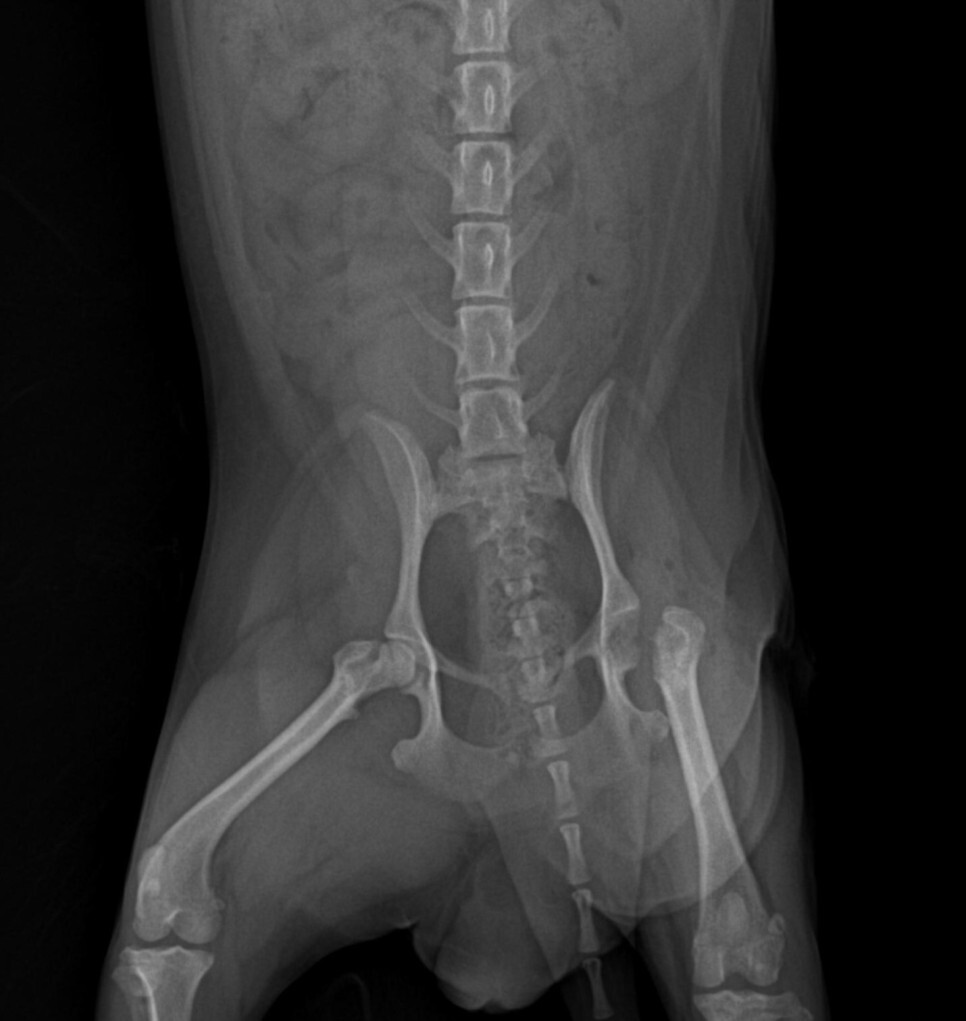

수술 후 매끄럽고 균질해야 할 골두 표면이 움푹

패여 있는 것을 확인할 수 있습니다.

대퇴골두절단술을 진행하게 되면 수술을 진행한

쪽의 다리가 약간 짧아지게 됩니다.

한쪽만 수술을 진행하는 경우 다리 길이

차이에 의한 약간의 파행 증상이 있을 수 있으나

심한 통증은 90% 이상 줄어들게 됩니다.

수술 이후의 증상은 통증에 의한 파행이라기

보다는 길이 차이에 의한 증상이라고 볼 수 있습니다.